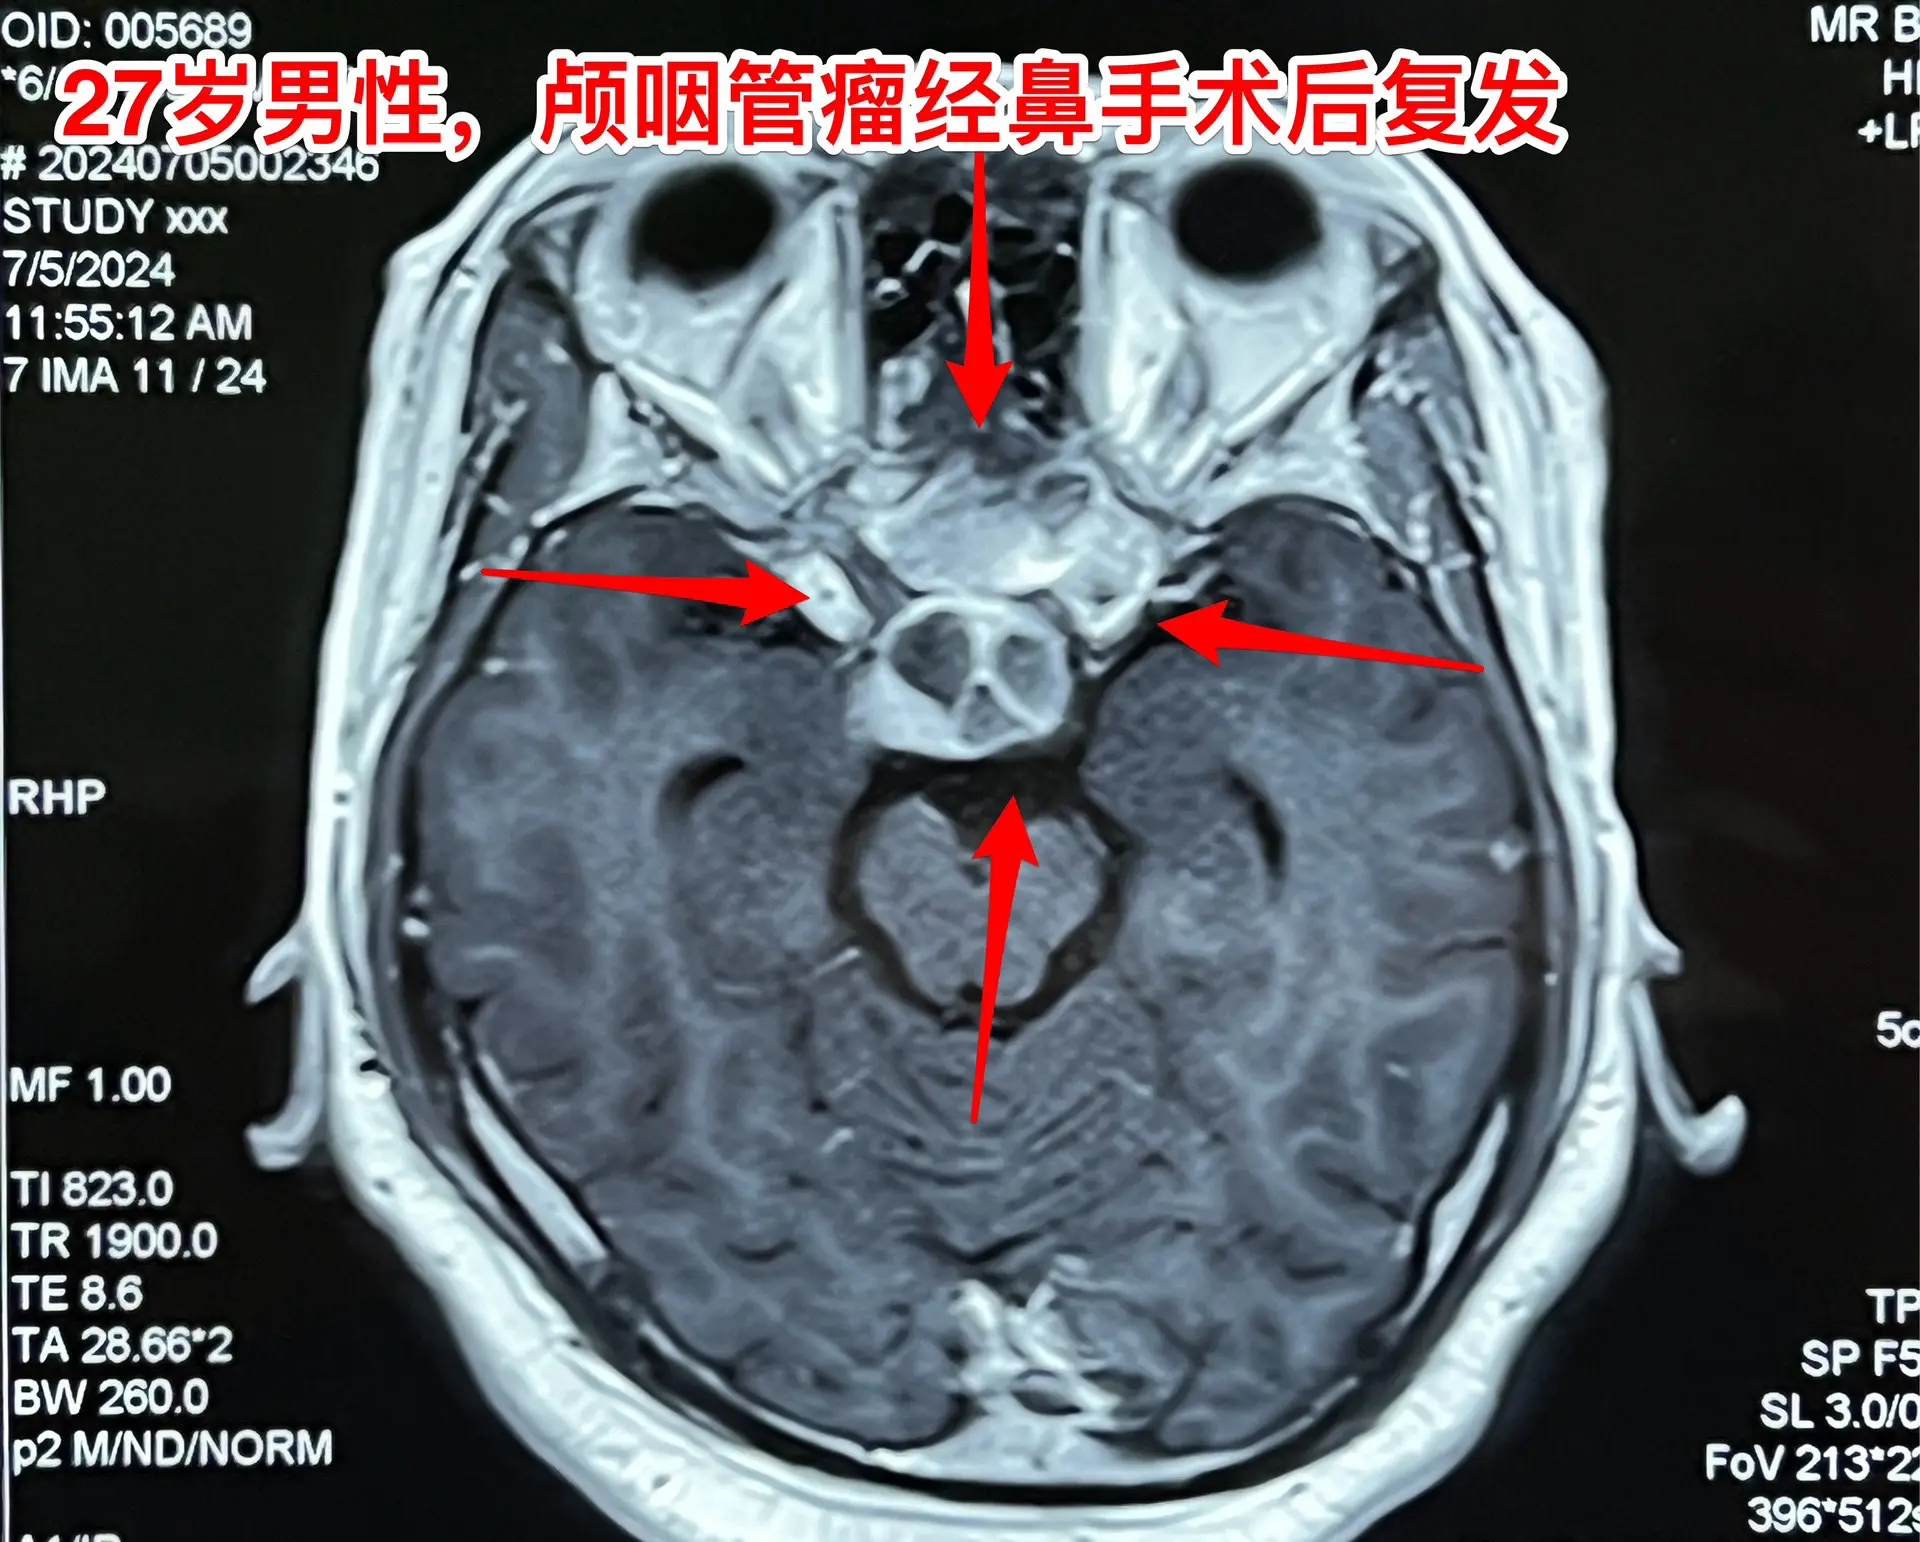

颅咽管瘤经鼻手术后8个月复发视力严重受损。27岁的甘肃小伙子因视力下降在外院诊断为颅咽管瘤,2023.11在兰州市某医院作了经鼻手术切除颅咽管瘤,肿瘤没有得到完全切除,视力稍有改善,出院后不久视力又呈下降趋势。2024年7月5日磁共振显示肿瘤体积很大。

头CT显示肿瘤密度稍高,没有钙化,见图5。患者视力很差,根本看不见视力表的第一行。看手机时手机几乎是贴着眼睛才能看见。